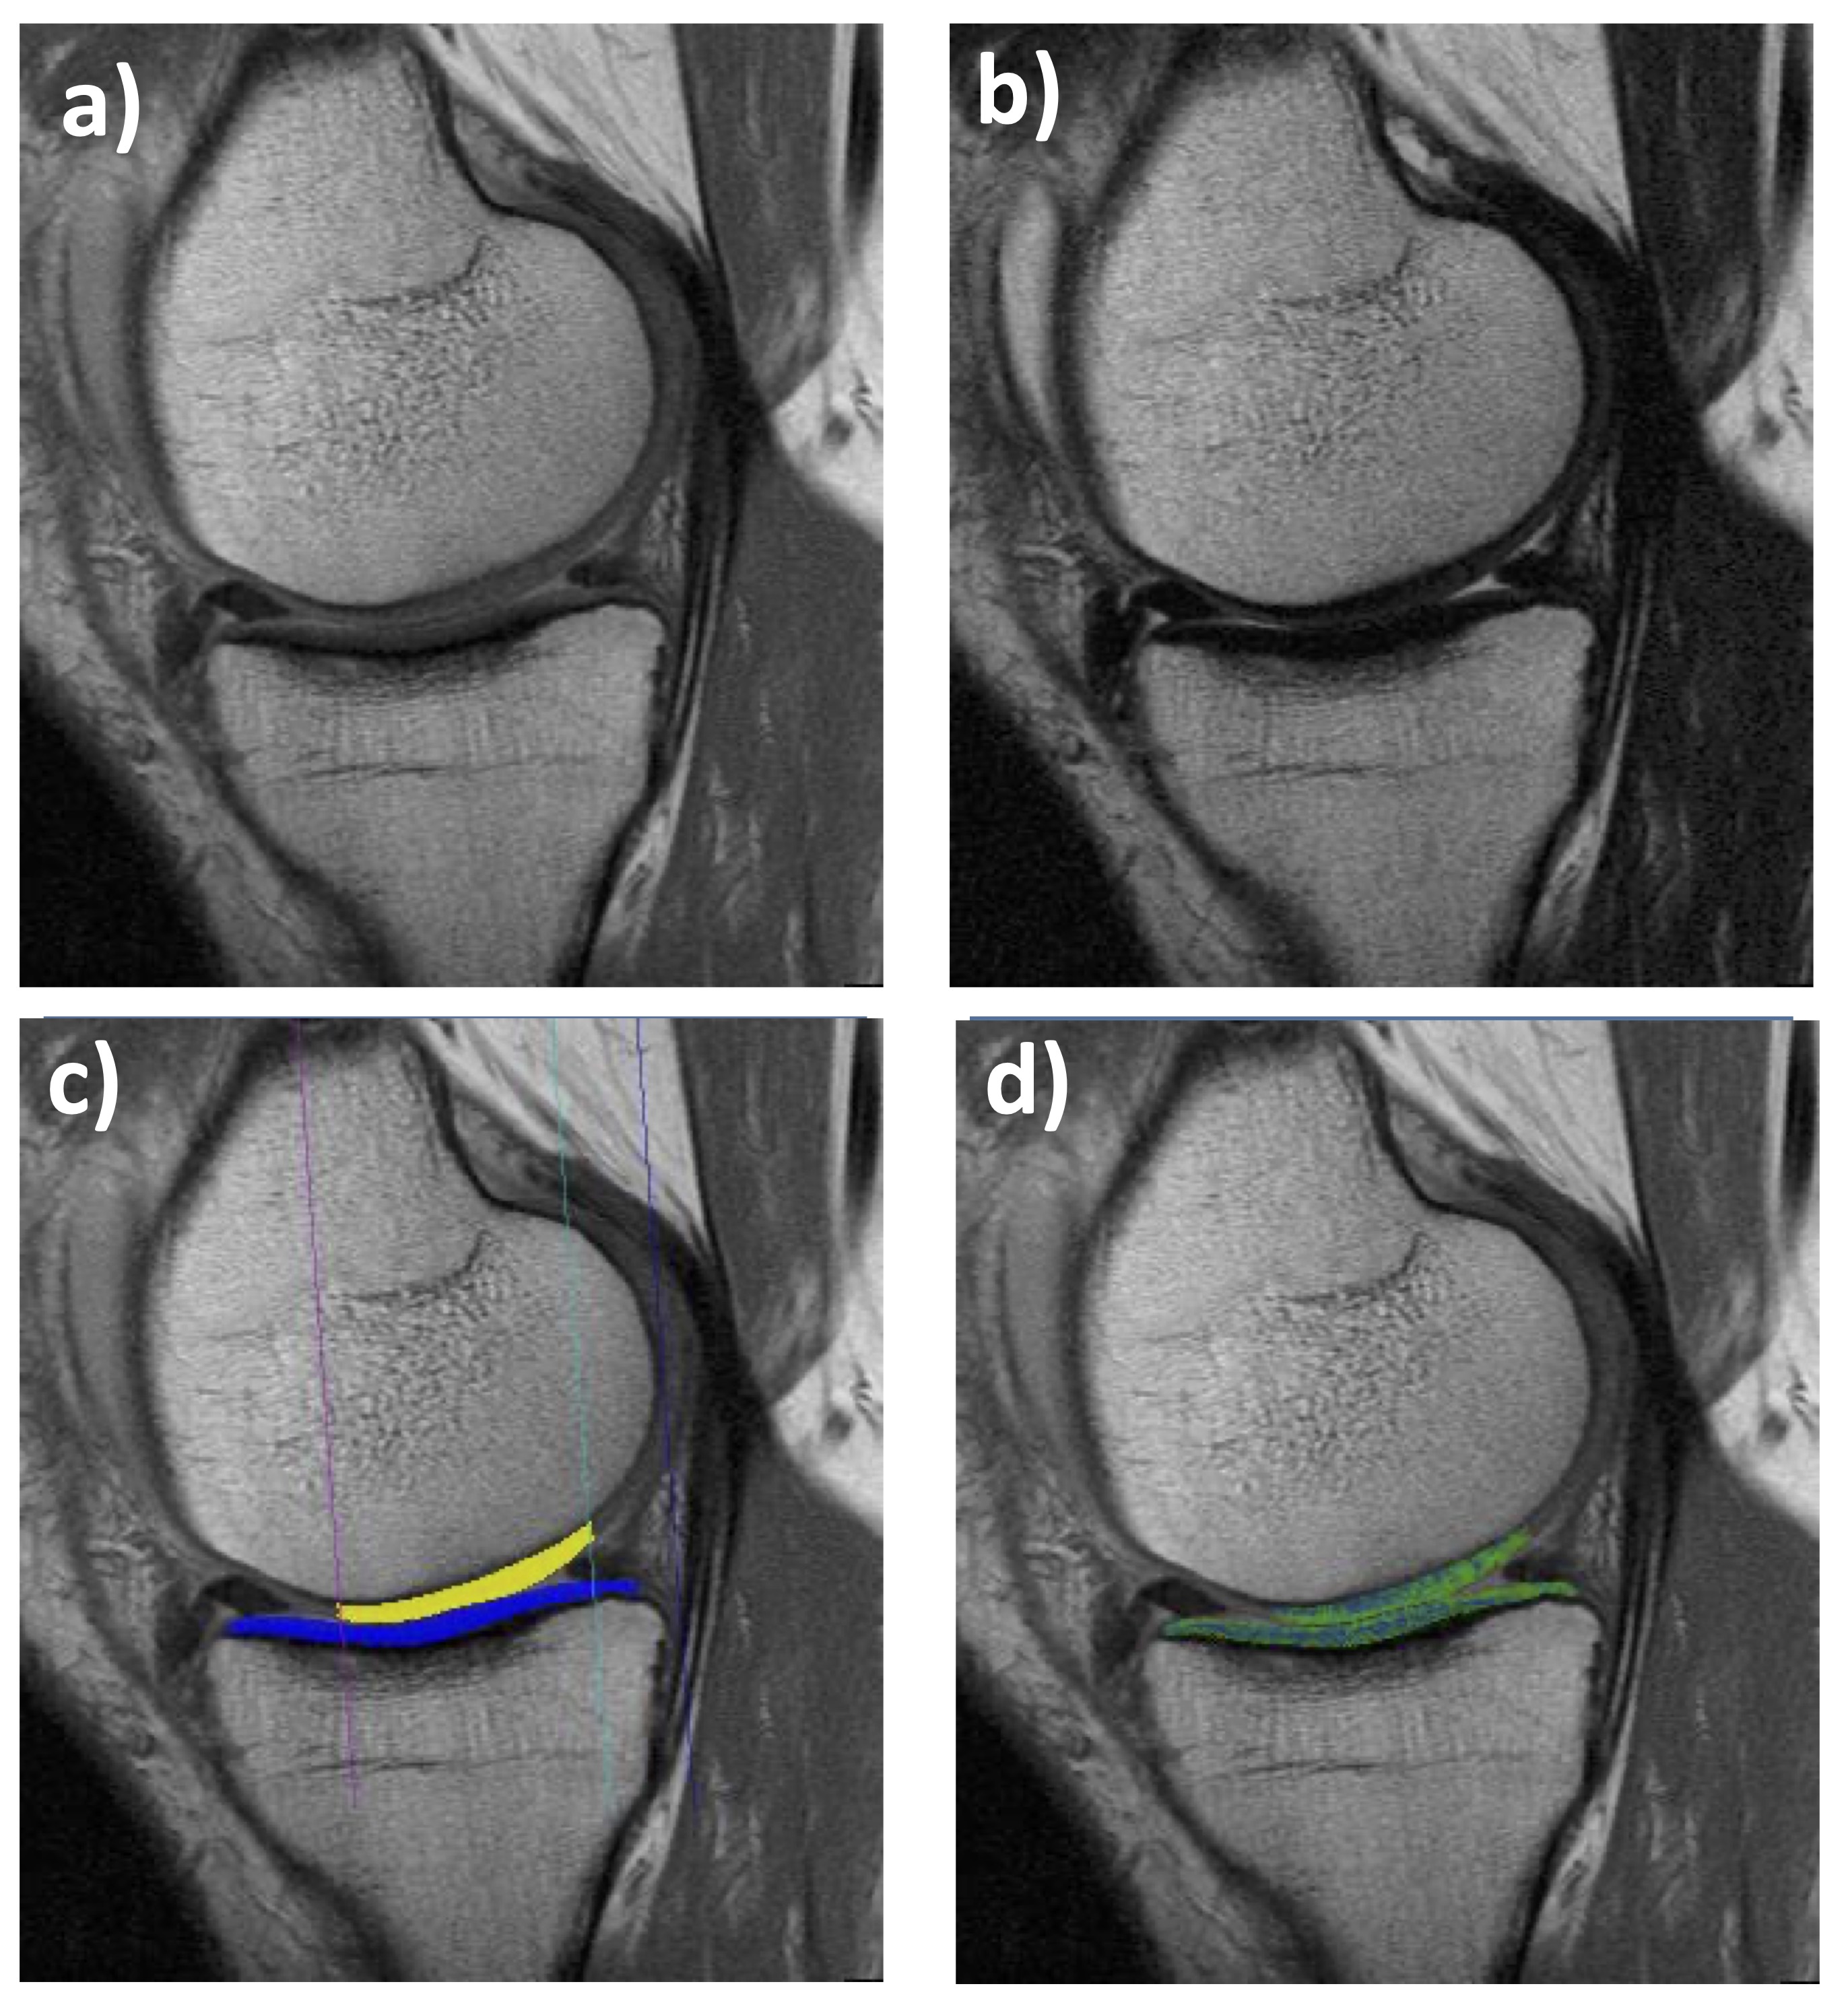

Figure 1. Sagittal multiple-echo spin-echo (MESE) MRI of the medial femorotibial compartment (MFTC): a) Shortest echo (10 ms); b) Longest echo (70 ms); c) Cartilage segmentation of the medial tibia (MT) and lateral tibia (LT); d)T2 map (only cartilage T2 is shown, no other structures)

From an MR image acquisition perspective, T2 maps can be generated by various spin echo or gradient echo techniques [4]; the most widely used is 2D multiple-echo spin-echo (MESE – Fig. 1). MESE uses 4-8 different echo times (TEs) to derive T2 on a voxel-by-voxel basis. Yet a more versatile 3D gradient echo-based sequence has recently been proposed, i.e. quantitative double echo at steady state (qDESS – Fig. 2) in combination with water excitation [23–28]. qDESS generates two echoes per repetition time (Fig. 2), separated by a spoiler gradient. An image is formed from each echo, and T2 can then be computed from changes in voxel signal intensity between the two sets of images. The image formed from the first echo displays mixed T1/T2 contrast, whereas the image formed from the second echo exhibits contrast with contributions from both T2 and diffusion effects. Conventional DESS[24, 29, 30] combines data from both echoes (Figs 2 a, b) to generate a single (fused) image with mixed T1-/T2-contrast (Fig. 2c), enabling morphometry but not relaxometry (T2). However, with a modification of the gradient fields and images from both echoes stored separately (qDESS), a voxel-by-voxel fit can generate the desired high-resolution T2 map (Fig. 2f). This approach has been validated versus single echo spin echo T2, the gold standard for this type of measurement [23–27].

Based on these initial findings, seed funding was obtained from the PMU FFF(F2 - Table 1; PMU FFF) to improve the usefulness and versatility in the technical implementation of the T2 analysis, by adding tools for measuring (up to 16) defined femorotibial subregions [40]. Further, the grant funded the application of such cartilage T2 relaxometry to explore some clinically relevant research questions. A series of three studies examined differences of subregional (laminar) cartilage T2 by age and sex in healthy subjects [41], between healthy and early OA samples [42], and between OA knees with and without substantial subsequent progression [43]. In almost 100 healthy subjects (age 45-78), cartilage T2 of the deep and superficial femorotibial cartilage was measured in the 16 defined femorotibial subregions (Fig. 1), using the MESE sequence [21, 29, 44]. Significant variation in femorotibial cartilage T2 between subregions was observed in both the superficial and deep cartilage layers, but no differences were observed between male or female cartilage, and between those below and above the median age (54y)[41]. This first study to report subregional (layer-specific) compositional variation of femorotibial cartilage T2 in healthy adults hence identifies significant differences in the superficial and deep cartilage T2 between femorotibial subregions; yet no relevant sex- or age-dependence of cartilage T2 was observed between age 45-78 years [41]. This suggests that common layer- and region-specific T2 reference values can be used to identify compositional pathology in joint disease across both sexes and for all age groups captured in the above range [41]. Exploring early OA (definite osteophytes on radiographs, but no radiographic joint space narrowing) and knees at risk (relevant factors of incident OA), we found no significant difference between those in either cartilage layer [42]. However, both those at risk and those with early (radiographic) OA displayed significantly longer cartilage T2 in the deep and superficial layers [42] than those in the healthy reference cohort [41]. We further studied laminar T2 subjects with medial femorotibial progression by both cartilage loss from quantitative MRI, and by joint space width (JSW) loss for semi-flexed weight-bearing radiographs in comparison with knees matched by sex, body mass index, baseline Kellgren-Lawrence-grade (KLG), and pain that did not display progression with either method anywhere in the joint [43]. At baseline, no statistically significant difference in deep or superficial cartilage T2 was observed between both groups, but the 1-year increase in deep (not superficial!) medial T2 that occurred concurrently was more pronounced in the progressor than in the non-progressor knees [43]. Thus, T2 did not appear to be a strong prognostic factor for subsequent structural progression in the same compartment of knees with established radiographic OA, when appropriately controlling for covariates, but deep cartilage longitudinal T2 change occurred concurrent with progression. The implementation of the subregional analysis approach was then used to examine the diagnostic performance of T2 across various pre-radiographic and radiographic OA strata [45]. Interestingly, peripheral (rather than central) subregions and superficial (rather than deep) cartilage T2 more efficiently differentiated various pre-radiographic OA stages. The hypothesis that the ratio of superficial vs. deep layer T2 or central vs. peripheral T2 can enhance diagnostic performance had to be refuted [46]. As previously done with cartilage thickness [47], the subregion approach was expanded to a location-independent analysis technique of cartilage T2 across the femorotibial joint. This method permits one to retrieve T2 times that express a weighted summary of the magnitude of the regional values (or longitudinal changes over time), independent of where they occur in the joint [48–50]. A cross sectional application revealed that location-independent laminar cartilage T2 analysis is equally sensitive to differences between healthy knees vs. those with radiographic OA as is subregional analysis [50]. Further, the method efficiently differentiated knees at various stages of radiographic OA, with the advantage that it does not rely on any “a priori” assumption about locations where the strongest differences may be observed [50]. Finally, no statistical penalty needs to be applied to account for performing parallel statistical tests for multiple endpoints. When applied longitudinally to the determination of T2 lengthening and shortening scores across the femorotibial joint [49], ordered values (of subregional T2 change over one year) revealed significant differences in both the superficial and deep cartilage layer between radiographic strata, whereas the region-specific T2 measures were insensitive to such differences in longitudinal change [48].